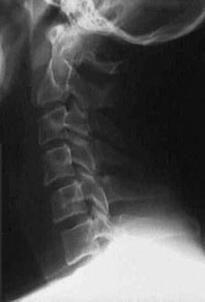

TRAUMA CERVICALA

Incidenta laterala Incidenta

laterala Incidenta

Aspect normal Imagine

incompleta Aspect

normal